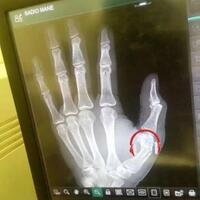

Sadio Mané broke his thumb while on duty for Senegal. He may miss LFC’s trip to Huddersfield this weekend